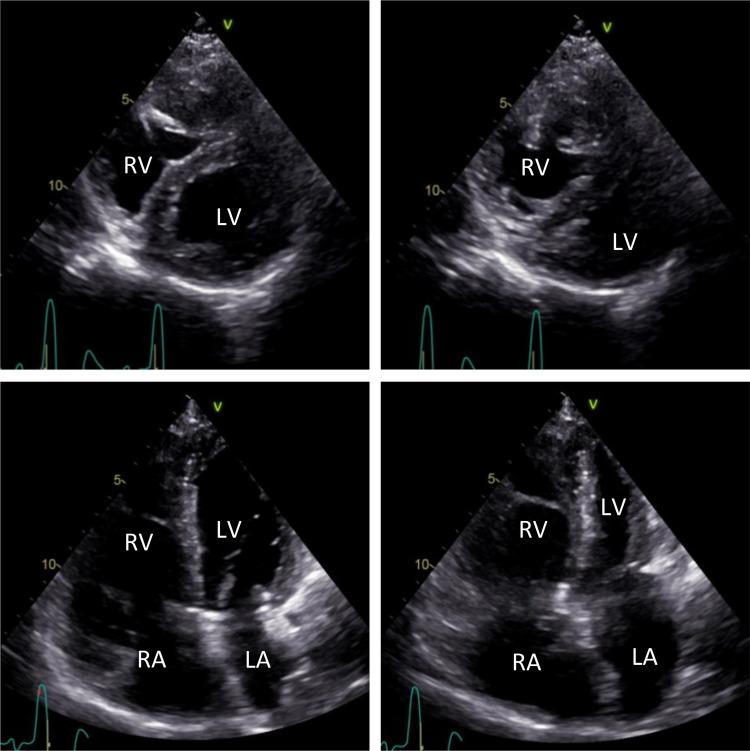

Primary pulmonary artery hypertension (PAH) is a clinical diagnosis that requires the exclusion of other underlying causes of pulmonary hypertension (PH). Increased pulmonary artery (PA) pressure and subsequent right ventricular (RV) pressure overload often result in a flattening of the curved interventricular septum, leading to a D-shaped left ventricle (LV), as observed in echocardiographic short-axis views. A similar finding may be also observed on myocardial perfusion SPECT images, the so-called Movahed's sign. We present a clinical case of a female patient with PAH and progression of exertional dyspnea that underwent myocardial perfusion SPECT to investigate LV myocardial ischemia. The SPECT images revealed enhanced tracer uptake in the dilated right ventricle. Additionally, we observed a D-shaped LV or Movahed's sign, which may serve as a potential marker of RV pressure overload, along with a small stress-induced perfusion defect on the LV septal wall. Our findings highlight the importance of considering the presence of a D-shaped LV and signs of RV pressure overload, as they can alter the interpretation of LV perfusion deficits on SPECT images. This case report aims to emphasize the complex nature of right heart abnormalities in pathologies such as PAH and the consideration of the RV implications in myocardial SPECT images-which typically focus solely on the LV.

原发性肺动脉高压(PAH)是一种临床诊断,需要排除肺动脉高压(PH)的其他潜在病因。肺动脉(PA)压力升高及随后的右心室(RV)压力过载常导致室间隔曲线变平,在超声心动图短轴视图中表现为左心室(LV)呈D形。在心肌灌注单光子发射计算机断层扫描(SPECT)图像上也可能观察到类似表现,即所谓的莫瓦赫德征。我们报告一例PAH女性患者的临床病例,该患者因劳力性呼吸困难加重接受心肌灌注SPECT检查以评估左心室心肌缺血情况。SPECT图像显示扩张的右心室放射性示踪剂摄取增强。此外,我们观察到左心室呈D形或莫瓦赫德征,这可能是右心室压力过载的潜在标志物,同时左心室间隔壁存在小的运动诱发灌注缺损。我们的研究结果强调了考虑左心室呈D形及右心室压力过载征象的重要性,因为它们可能改变对SPECT图像上左心室灌注缺损的解读。本病例报告旨在强调PAH等疾病中右心异常的复杂性,以及在心肌SPECT图像中考虑右心室影响的必要性,因为心肌SPECT图像通常仅关注左心室。